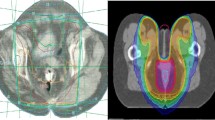

Advancements in radiation treatment over time have attempted to better optimize its delivery to potentially reduce toxicity and allow for maximal dose escalation. Historically, two-dimensional techniques based on surface anatomy and bony landmarks were used to deliver radiation for anal cancer. Until recently, three-dimensional conformal radiation (3D-CRT) was the most commonly utilized treatment modality, incorporating CT imaging data to better identify the intended target. Intensity-modulated radiation therapy (IMRT) followed, which can be used to design still more conformal radiation fields. By modulating the intensity of each beam delivered, a dose can be designed to target the concavities and convexities of a tumor volume, thereby further reducing dose to adjacent tissues.

All patients underwent CT simulation, either prone with a belly board or supine. Non-IMRT radiotherapy planning followed classic two-dimensional radiotherapy borders for mini-pelvic fields, cone downs, and tumor boosts [19]. Electrons were used to supplement dose to the inguinal lymph nodes. IMRT contours and dose constraints were according to RTOG 05-29 [20]. Briefly, contours including the gross tumor, and elective lymph node regions (inguinal, internal iliac, external iliac) were defined using imaging studies with appropriate margin expansions for CTV and PTV. Total dose was 50.4 Gy for T2, 54 Gy for T3–T4, and 45 Gy for elective lymph node regions.